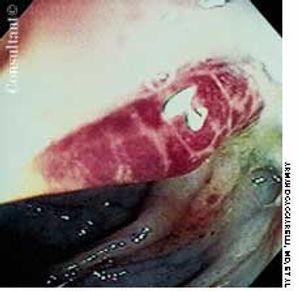

A 2-week history of diarrhea mixed with bright red blood was the presenting complaint of a 40-year-old man who was seropositive for HIV. Stool studies and culture results were negative for microorganisms. Colonoscopy demonstrated only the raised vascular lesion seen here in the sigmoid colon, which may have been responsible for the bleeding.